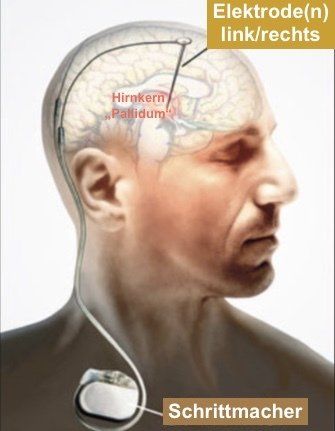

Bei der Tiefen Hirnstimulation (kurz THS) handelt es ich um einen neurochirurgischen Eingriff am Gehirn, bei dem bei Dystoniebetroffenen Elektroden in das Tiefe Hirn - genau genommen in die motorische Zentralschaltstelle, also die Basalganglien - implantiert bekommen. Bei Dystonie werden diese regelmäßig in der linken wie rechten Hirnhälfte im "internen Palladium", einem jeweils winzigen Areal in den Basalganglien, platziert und über Kabel mit dem Impulsgeber (Schrittmacher) verbunden.

Der Impulsgeber wird grundsätzlich rechts unterhalb vom Schlüsselbein oder in den Bauchraum unter die Haut gesetzt und dort an der äußeren Schicht eines Muskels befestigt. Rechts, weil die linke Seite grundsätzlich für die etwaige Implantation von Herzschrittmacher freigehalten wird. Ausnahmen sind indes möglich.

Nach Inbetriebnahme der THS vermögen die vom Impulsgeber generierten hochfrequenten, elektrischen Impulse auf eine Weise auf die Basalganglien Einfluss zu nehmen, die zur Folge hat, dass jene hemmenden Impulse, die das interne Pallidum bei gesunden Menschen auf natürliche Weise vom internen Pallidium aussendet, bei Dystoniebetroffenen imitiert werden.

Medizintechnisch besteht eine Tiefe Hirnstimulation aus drei wesentlichen Komponenten: Wenigstens zwei Elektroden, zwei Kabelverbindungen und ein Impulsgeber.

Der Impulsgeber, auch Schrittmacher genannt, wird grundsätzlich unter dem rechten Schlüsselbein unter der Haut eingesetzt. Er ist etwa 6cm x 6cm groß und von außen deutlich sichtbar. Von ihm führen Kabel den Hals entlang, hinterm Ohr vorbei auf die Schädeldecke, wo eine Verbindung mit den Elektroden hergestellt wird.